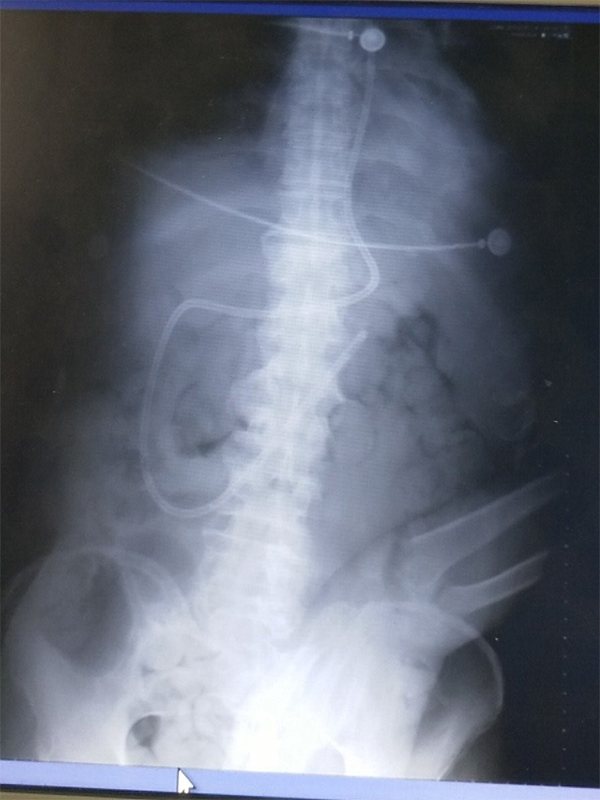

ICU

85 《 》 ICU